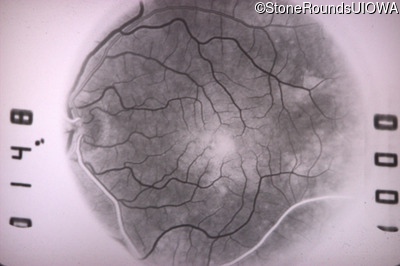

Fluorescein Angiography - Left - 20/20 -1 sc

Exemplar